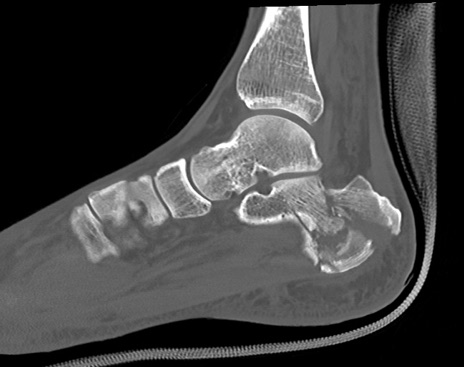

症例37 左足関節CT(矢状断像)

左足関節CT

冠状断像